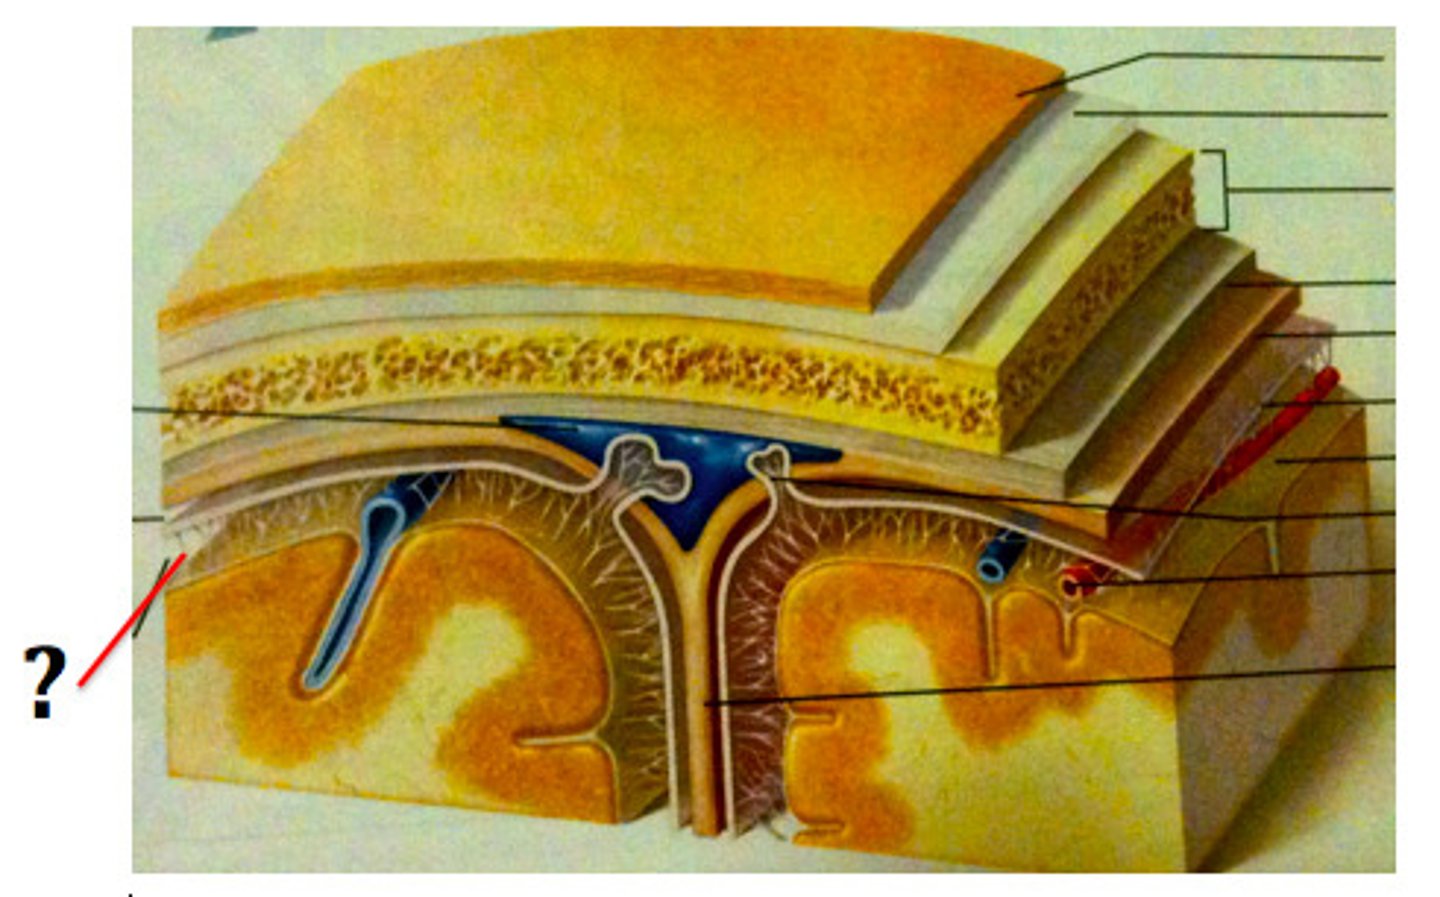

dural folds

Folded inner layer of dura mater

Extend into cranial cavity

Stabilize and support brain

subdural space

below the dura mater

potential space (if you have a head injury

the blood goes into the subdural space)

falx cerebri

separates the two hemispheres of the cerebrum

tentorium cerebelli

horizontal dural fold over cerebellum and in transverse fissure

falx cerebelli

separates the two hemispheres of the cerebellum